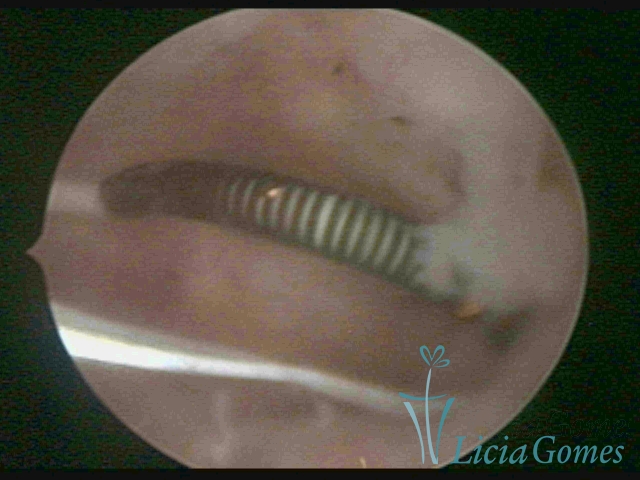

Cavity with Mirena®, being removed under direct view